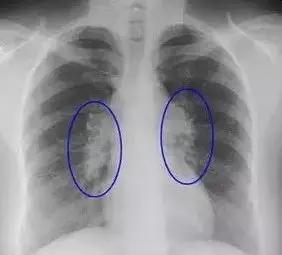

结节:大部分都是良性的在影像检查中(如CT、胸片),发现类圆形的直径小于3厘米的病灶通常描述为结节灶,直径小于1厘米时常被描述为“小结节”,直径小于0.5厘米时就称为微小或细小结节。随着近年来多排螺旋CT的出现,小结节或微小结节发现得越来越多,但大部分是良性的。

肺部结节:一般年龄大、肺部有基础疾病的人,做检查易发现肺部结节。即使发现肺部结节也不必恐慌,因为其中只有极少部分人最后被证实是肺癌。此时必须找专业医生鉴别判断:对于小于5毫米的微小结节,仅做随访观察,3个月到半年重新做一次CT检查。如结节没有变化、没有异常增大,一般被认为是没有风险的,有的甚至会随着时间变化慢慢消失。1厘米以上的大结节,建议要尽早诊治。